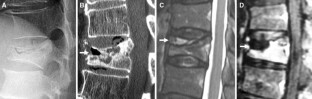

Percutaneous vertebroplasty was prospectively performed for 244 patients with OVCF with IVC; 30 had DND and 214 did not. Radiographic parameters of local kyphotic angle, percent spinal canal compromise and intravertebral instability were investigated for correlations to DND. Procedural outcomes were evaluated using visual analog scale (VAS), Oswestry Disability Index (ODI), and modified Frankel grades.

Before vertebroplasty, no substantial difference in local kyphotic angle was seen between OVCF with IVC with and without DND, but percent spinal canal compromise and intravertebral instability were greater in OVCF with IVC with DND (P < 0.001). After vertebroplasty, 25 of 30 cases (84 %) of OVCF with IVC with DND achieved clinically meaningful improvement (CMI), but 5 (17 %) did not. Patients with CMI showed substantial improvements in intravertebral instability (P < 0.001), and no change in local kyphotic angle or percent spinal canal compromise. In five patients without CMI, four showed an initial improvement, but subsequent vertebral fracture adjacent to the treated vertebra caused neurologic re-deterioration. One patient with percent spinal canal compromise 54.9 % and intravertebral instability 4° achieved no neurologic improvement following vertebroplasty. No serious complications or adverse events related to the procedure were encountered.